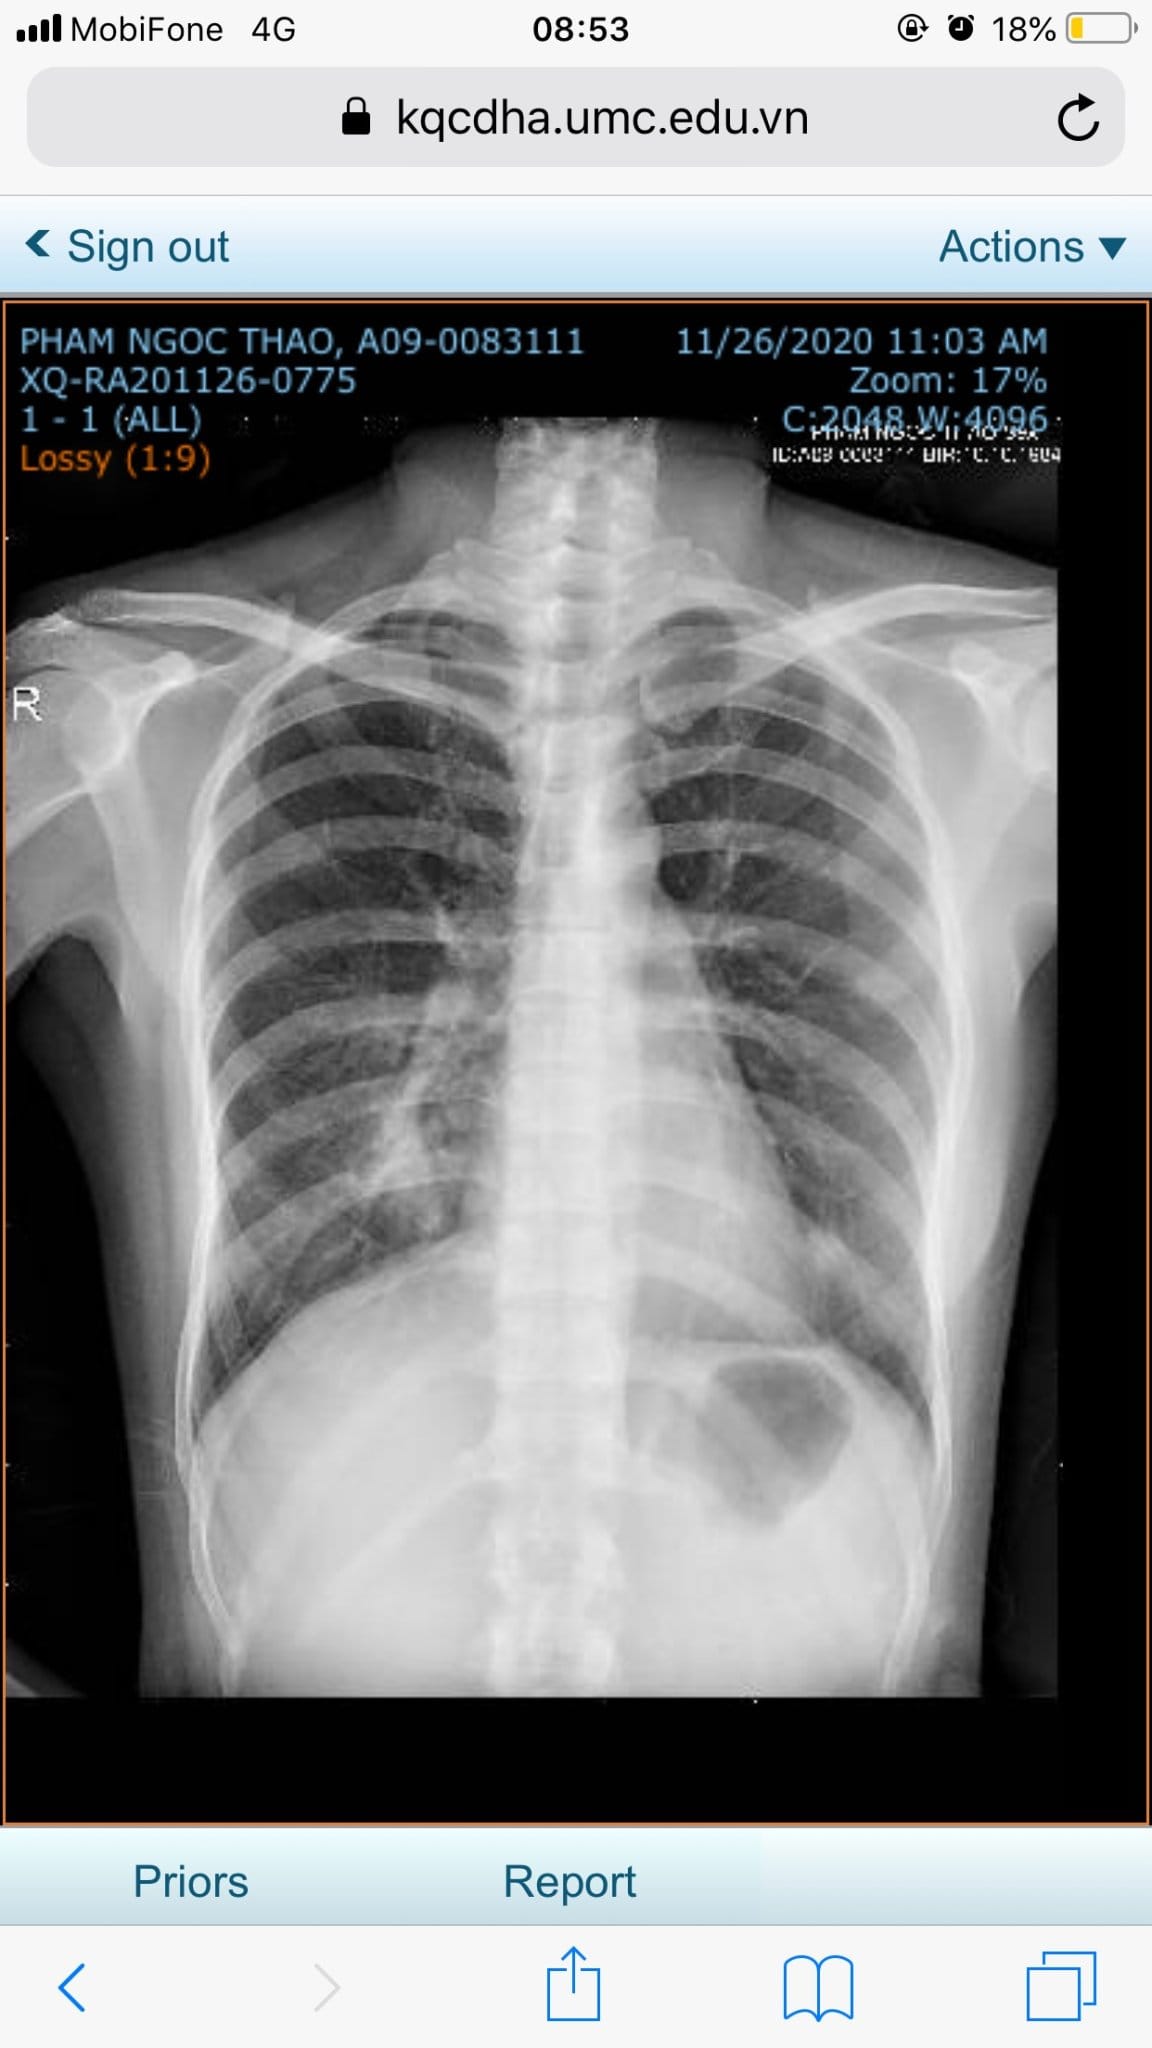

Kết quả X quang của bệnh nhân trước khi chăm sóc sức khỏe bằng Năng lượng sinh học vào ngày 26/11/2020